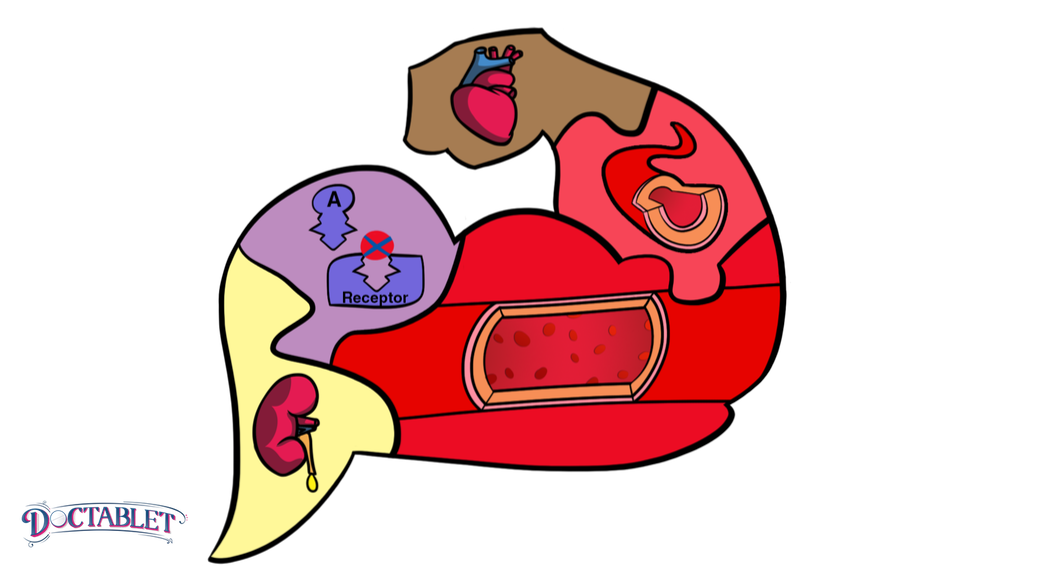

Una de cada tres personas sufre de presión alta. Muchas personas la tienen por varios años sin saberlo, ya que la padecen sin que les provoque síntomas. Pero aunque usted no presenta ningunos síntomas, al pasar el tiempo, la hipertensión no tratada deteriora diferentes partes de su cuerpo; incluyendo arterias, órganos y cerebro. Una vez su médico haya confirmado que usted tiene hipertensión, el próximo paso es comenzar medicina para la presión alta. Dependiendo de su nivel de presión arterial, su doctor decidirá darle más de un medicamento para la hipertensión. Esto no es infrecuente. La mayoría de las personas necesitan al menos dos medicamentos diferentes para tratar la presión arterial alta y muchos necesitan tres o más. Esto se debe a que los medicamentos para la presión arterial encajan entre sí como un rompecabezas. Las piezas trabajan juntas para producir combinaciones efectivas. Pase lo que pase al momento de escoger los medicamentos, los objetivos del tratamiento son siempre los mismos:

Repasemos los diferentes tipos de medicamentos disponibles para tratar la presión alta, sus nombres y efectos secundarios comunes.

Bloqueadores beta

Ejemplos: Atenolol, Metoprolol (y otros medicamentos que terminan en «lol»)

Estos medicamentos equivalen a un freno de mano para el cuerpo y pueden tranquilizar las cosas, lo cual causa que algunas personas sufran fatiga. También, pueden desencadenar sibilancia o jadeo en pacientes que sufren de enfisema o bronquitis crónica y asma. Dicho esto, muchas personas que toman bloqueadores beta en dosis bajas no sufren muchos efectos secundarios. Por su cuenta, raramente disminuyen la presión arterial a la meta deseada, y a menudo requieren otras piezas para completar el rompecabezas.

Inhibidor de la Enzima Convertidora de Angiotensina o “Inhibidores de la ECA”

Ejemplos: Enalapril, Benazapril (y otros medicamentos que terminan en «pril»)

Inhibidores de la ECA son buenos solos y hasta mejor cuando se combinan. Pueden causar tos en algunas personas que los toman. Aunque no es una tos peligrosa, puede molestar a aquellos que la desarrollan. La tos es seca y con picor. Si usted está sufriendo de una similar y los toma, debería decirle a su doctor. Uno de los problemas más importantes de este tipo de medicamentos es que pueden elevar el potasio, sobre todo si sus riñones no están saludables. Su médico tal vez querrá controlar esto con un examen de sangre, si ese es el caso para usted.

Bloqueadores del receptores de angiotesina

Ejemplos: Losartán, Irbersartan (y otros medicamentos que terminan en «sartan»)

Lo mejor de estos medicamentos es que raramente producen efectos secundarios. Por esta razón se desarrollaron. Por otra parte, no son medicamentos muy potentes para bajar la presión arterial cuando se utilizan solos. La mayoría de ellos no bajan la presión arterial sin la adición de otras piezas al rompecabezas. Al igual que los IECA, pueden elevar el potasio, y esto se convierte en un motivo de preocupación si sus riñones están débiles.

Bloqueadores de los canales de calcio.

Ejemplos: Amlodipina (y otros medicamentos con «Pina»)

Los «BCC», como se denominan a veces, son una necesidad para cada rompecabezas de hipertensión efectivo. Raramente causan efectos secundarios en dosis pequeñas, pero en dosis más altas pueden causar una hinchazón en sus piernas. Esto NO es algo que le hará daño, pero puede ser molesto para aquellos que lo sufran.